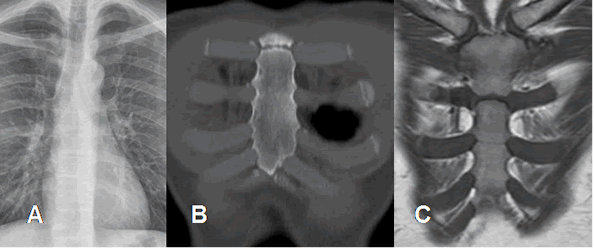

Fig 14. Esternón normal.

A: Rx PA. Esternón no visible directamente.

B: TAC reconstrucción coronal. Hueso normal.

C: RM coronal en T1. Esternón hipointenso por predominio de medula osea roja.